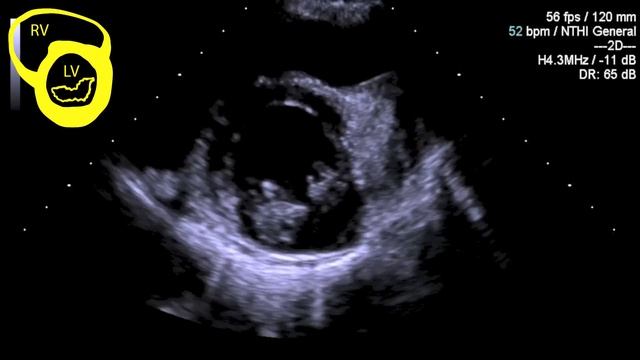

The video provides a step-wise approach to performing Level 1+ trans-thoracic echocardiography. This approach is useful for critical care practitioners,...